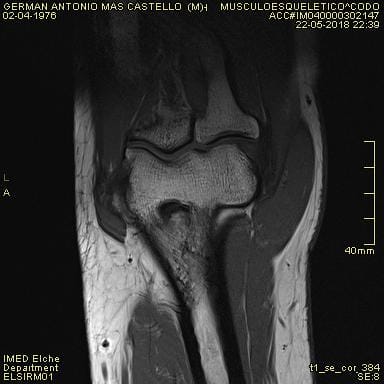

¿Quién me puede echar una mano con una resonancia magnética de tedon de bíceps en codo?

la mutua no se pone de acuerdo con el hospital y me tienen mareado, ¿alguien me echa una mano para saber lo que puedo tener en el codo? Dispongo de más fotos, pero no se cual indicar para que puedan ver algo. Muchas gracias de antemano